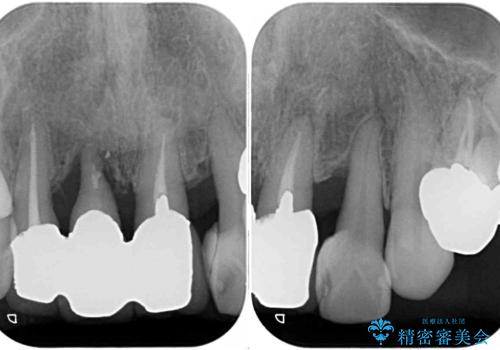

- 上顎前歯の違和感や不快感を気にして来院された患者様です。

現在のクラウンは金属の縁が見えており、歯と歯と歯肉の間に大きなスペースができていて、見た目も悪く、物が挟まったり話しにくかったりしていました。

また、前歯に抜歯が必要な歯があったため、抜歯をし、傷の治りを待ってオールセラミックブリッジにて補綴治療を行うこととしました。